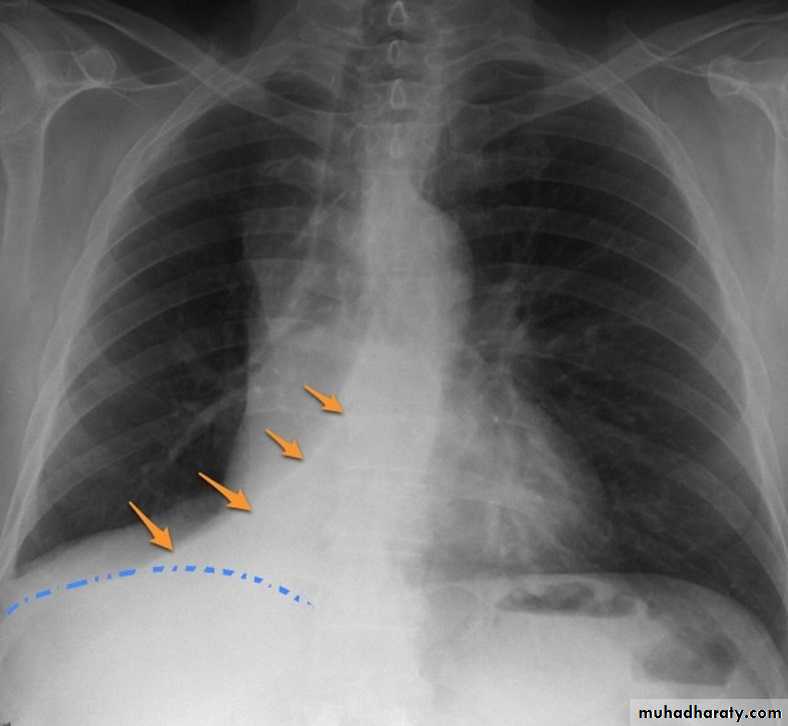

RT lower lobe collapse

usually the medial aspect of the dome of right hemidiaphragm is lost.

the right hilum is depressed

It is important to note that the right heart border, which is contacted by the right middle lobe remains well seen.

Left lower lobe collapse has distinctive features, and can be readily identified on frontal chest radiographs, provided attention is paid to the normal cardiomediastinal contours. The shadow cast by the heart does however make it harder to see than the right lower lobe collapse

Radiographic features

Left lower lobe collapse

is readily identified in a well penetrated film of a patient with normal sized heart, but can be challenging in the typical patient with collapse, namely unwell patients, with portable (AP) often under-penetrated films, often with concomitant cardiomegaly. Features to be observed include :

triangular opacity in the posteromedial aspect of the left lung

edge of collapsed lung may create a 'double cardiac contour'

left hilum will be depressed

loss of the normal left hemidaphgragmatic outline

loss of the outline of the descending aorta

Non-specific signs indicating left sided atelectasis are usually also be present including:

elevation of the hemidiaphragm

crowding of the left sided ribs

shift of the mediastinum to the left

On lateral projection the left hemidiaphragmatic outline is lost posteriorly and the lower thoracic vertebrae appear denser than normal (they are usually more radiolucent than the upper vertebrae) .